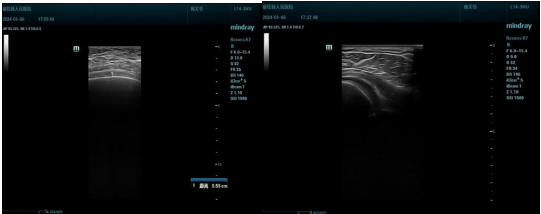

治疗前

治疗后